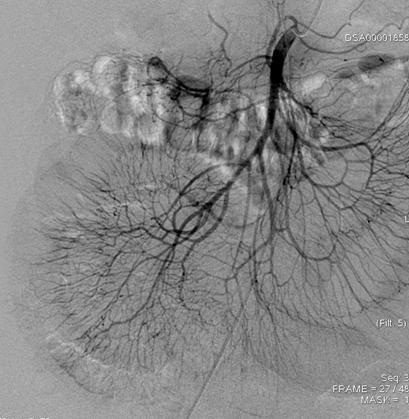

图1. 肠系膜动脉造影(DSA)

图2. 风湿免疫指标办好住院已经是1月13日下午四点了,介入科方淳主任及团队加班加点,当天晚上就为患者做了肠系膜动脉和静脉造影,结果没有发现大血管的问题,但是小血管充血、丰富,呈梳子样改变(称为“梳子征”,图1)。排除了肠系膜大血管的问题之后,高度怀疑肠系膜小血管炎可能,事不宜迟,赵家胜主任通过电话联系到风湿免疫科值夜班的王璇主治医生,王医生仔细询问了病史,了解到患者有过脱发和自发性流产的病史,结合本次肠道小血管炎的表现,高度怀疑系统性红斑狼疮引起的肠系膜血管炎。为了缓解患者的腹痛,挽救病人的生命,王璇医生基于对病情的判断,在化验结果尚未出来的情况下果断使用了糖皮质激素,第二天早上(1月14日)患者腹痛和恶心、呕吐即明显好转,患者胃口也开了,随后吃了点半流质,但下午又出现了腹痛和呕吐,这时化验结果也出来了(见图2),狼疮的标志性抗体-抗Sm抗体和ds-DNA抗体均阳性,证实了系统性红斑狼疮的诊断。赵主任和风湿免疫科汤建平主任共同查房后认为系统性红斑狼疮诊断明确,以急性腹痛起病,而且一发病就表现为狼疮危象的红斑狼疮少见,常规剂量激素疗效不佳,腹部CT结果显示肠壁水肿和胸腹水有进展(见图3、图4),需要立即进行大剂量激素冲击治疗。